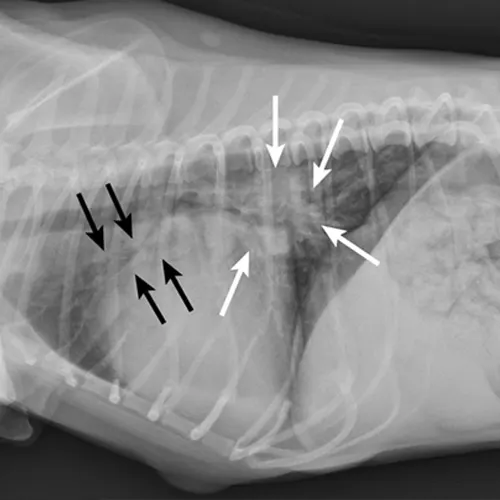

Primary cardiac disease that leads to CHF-related pulmonary edema commonly causes diffuse (perihilar in the dog) or variable (in the cat) interstitial and alveolar patterns. The vertebral heart score (VHS) is an objective method for evaluating the size of the cardiac silhouette (see Steps to Measure VHS). Certain cutoff values are used to determine whether acute respiratory distress is primarily pulmonary or cardiac in origin and to guide initial therapy for stabilization and planning for definitive cardiac or respiratory workup. A VHS <11.4 in the dog can help rule out mitral valve disease–related CHF as a cause for respiratory signs.3 Although an increased VHS can be associated with primary cardiac disease, it is not a specific characteristic in small-breed dogs because of their thoracic conformation.3 In the cat, a left lateral VHS ≤7.9 can reasonably rule out the presence of heart disease.4 Additional radiographic changes associated with primary cardiac disease include left atrial enlargement and pulmonary venous distension (Figures 1 and 2). Pleural effusion can be associated with CHF and primary pulmonary disease. A miliary pattern and/or solitary soft tissue densities in the lungs are indicative of primary pulmonary disease (Figure 3). Hyperinflation of the lung and distinct peribronchial markings are supportive of lower airway disease, although peribronchial markings can be found in the cat with CHF.

Mixed cardiac and pulmonary disease can exist in small animals with respiratory distress. For example, a dog may be presented with a history of mitral valve insufficiency but have clinical and radiographic evidence of aspiration pneumonia following a dental prophylaxis; or, a cat may present with a heart murmur and evidence of lower airway disease based on breathing pattern and thoracic radiographs (Figure 4; see image gallery above).